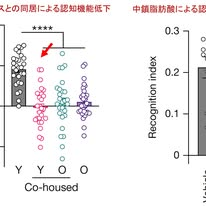

著者らはまず,加齢に伴う腸内細菌の変化が認知機能に影響するかどうかを検討しました.若いマウスと老齢マウスを同居させると腸内細菌叢が共有されますが,その結果,若いマウスであっても記憶課題の成績が低下することが分かりました.新奇物体認識試験では,若齢マウスは新しい物体をよく探索するのに対し,老齢マウスや「老齢マウスと同居した若齢マウス」では識別能力が低下していました(図1左).この結果は,認知機能低下の一部が腸内細菌叢の加齢変化によって引き起こされる可能性を示しています.

次に著者らは,どの細菌がこの現象に関与するのかを詳細に解析しました.その結果,加齢とともに増加し若いマウスにも伝播する細菌として Parabacteroides goldsteinii(腸内に生息するグラム陰性の偏性嫌気性桿菌)が同定されました.この細菌を若いマウスに定着させると,若齢であっても記憶機能が低下しました.この結果は,腸内細菌の特定の種が認知機能に直接影響する可能性を示しています.

さらに著者らは,この細菌がどのようにして脳機能に影響するのかを調べました.その結果,この細菌は中鎖脂肪酸(medium-chain fatty acids:MCFA)を産生し,その代謝物が認知機能に影響することが分かりました.培養上清のメタボローム解析から,3-hydroxyoctanoic acid(3-HOA)などのMCFAが増加していることが確認されました.この代謝物をマウスに投与すると,海馬の神経活動が低下し,新奇物体認識試験でも記憶成績が低下しました(図1右).

さらに重要なのは,この作用が免疫系と迷走神経を介して起こることです.MCFAは免疫細胞に発現するGPR84受容体を活性化し,TNFやIL-1βなどの炎症性サイトカインを誘導します.これらの炎症シグナルは迷走神経求心路の活動を低下させ,その結果として脳幹の孤束核や海馬の神経活動が低下します.この一連の変化により,記憶形成に重要な海馬の神経活動が抑制されると考えられました(図2).

この研究の重要な点は,認知機能低下が必ずしも脳内の病理だけで説明されるものではなく,腸内細菌,免疫系,迷走神経を介した全身的な生理機構と密接に関係していることを示した点にあります.すなわち,腸の状態が迷走神経を通じて脳の活動を調節し,最終的に海馬の記憶形成に影響するという「腸―免疫―迷走神経―海馬」という新しい概念が提示されたと言えます.腸は認知機能を保つために大切だと分かりました.